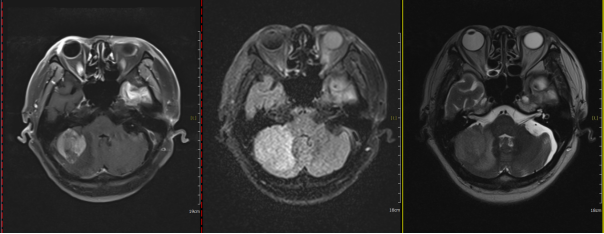

Figure 3: Before treatment, a space-occupying lesion in the right cerebellar hemisphere with an axial diameter of approximately 3.8 cm x 3.4 cm.

Figure 4: After treatment, a space-occupying lesion in the right cerebellar hemisphere with an axial diameter of approximately 2.1 cm x 1.7 cm.

Figure 5: Three months after radiotherapy, the right cerebellar hemisphere shows a lesion with an axial diameter of approximately 2.1 cm x 1.5 cm.